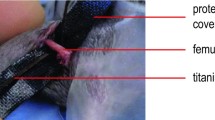

12 week old C57BL/6J male and female mice with an average weight of 25 g were used for this project. Surgical steps were performed, as previously described [26].

In preparation of surgical procedure, the right leg was shaved and disinfected. A 4 mm medial parapatellar incision was placed and the patella was dislocated laterally. Then a 0.5 mm hole was drilled into the intracondylar notch of the femur and a distally flattened 24G needle was implanted intramedullary into the right femur of the animal. Then the implanted pin was flattened at the distal end to prevent secondary pin loss. Then the patella was replaced and the wound was closed. After implantation of the pin a second incision was made in the middle of the lateral thigh. The musculus quadriceps was lateralized and the femur was exposed. Afterwards, a custom-made clip of 6 mm length was implanted into the ventro-dorsal femur. Then an osteotomy with a gap size of 1.8 mm was created in the non-union group with a fine drilling device [proxxon micromot 50, proxxon, Trier (Germany)] between the metallic clip using size-standardized spherical trephines under permanent saline cooling to prevent thermal damage around the defect site. In the control group a gap size of 0.25 mm was created accordingly with a Gigli saw [Gigli saw wire, 0,25 mm, AO Research Institute, Davos (Switzerland)]. The small gap size of 0.25 mm in the control group was mimicking physiological bone regeneration after bone fractures. The metallic clip inserted before guaranteed maintenance of the gap size. The gap sizes was controlled by custom-made template of 1.8 mm. The periosteum of the fracture site was left intact. Afterwards the wound was closed.